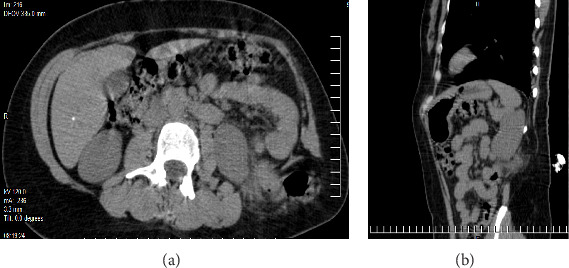

背景:Grynfelt 腰疝是所有腹壁疝中最罕见的一种,占病例的 1.5% 到 2%,迄今为止仅描述过 300 到 350 例。腰疝可以是先天性的,也可以是后天性的,通常由外伤或手术(先天性)引发。诊断依据临床表现,并通过计算机断层扫描确诊。需要进行手术治疗,通过开腹或腹腔镜手术进行修补。材料与方法:本病例为一名年轻女性,既往无手术史,也无外伤史,诊断为 Grynfelt 疝。手术结果患者接受了选择性左腰部切除手术,并使用腹膜上聚丙烯网片进行了疝成形术。术后恢复良好,术后 4 小时即可出院。普外科门诊分别在 20 天、1 个月、3 个月和 6 个月进行了随访,没有发现复发、并发症或事故。结论Grynfelt疝是一种罕见病,需要高度怀疑才能准确诊断。虽然病例通常没有症状,但未经治疗的疝气可导致严重的发病率。早期识别和及时手术治疗对于缓解症状和预防并发症至关重要。在本病例报告中,手术治疗包括通过左腰部切开术进行疝成形术,修补疝缺损并缩小疝内容物。为确保充分闭合,还放置了上腹膜网片。鉴于这种病症的罕见性,文献中没有具体的治疗指南。因此,这种类型的修补术是根据术中发现决定的。需要进一步开展研究,以明确管理策略,优化 Grynfelt 疝患者的治疗效果。

Background: Grynfelt's lumbar hernia is the rarest of all abdominal wall hernias, accounting for between 1.5% and 2% of cases, with only 300-350 instances described to date. Lumbar hernias can be congenital or acquired, often triggered by trauma or surgery (iatrogenic). Diagnosis is clinical and confirmed via computed tomography. Surgical intervention is required for resolution, with repair performed either through open or laparoscopic surgery. Material and Methods: We present the case of a young female with no prior surgical or traumatic history, in whom the diagnosis of Grynfelt's hernia was made. Results: The patient underwent elective left lumbotomy surgery with hernioplasty using a supra-aponeurotic polypropylene mesh. Postsurgical recovery was adequate, and she was discharged 4 h after surgery. Follow-up in the general surgery outpatient clinic occurred at 20 days, 1, 3, and 6 months, with no recurrence, complications, or incidents. Conclusion: Grynfelt's hernia is a rare entity that requires a high index of suspicion for accurate diagnosis. Although cases are often asymptomatic, untreated hernias can lead to significant morbidity. Early recognition and timely surgical intervention are crucial for symptom relief and prevention of complications. In this case report, surgical management involved hernioplasty through a left lumbotomy approach, repairing the hernia defect and reducing the hernia content. Supra-aponeurotic mesh was placed to ensure adequate closure. Given the rarity of this pathology, no specific management guidelines exist in the literature. Therefore, the decision for this type of repair was based on intraoperative findings. Further research is needed to clarify management strategies and optimize outcomes for patients with Grynfelt's hernia.